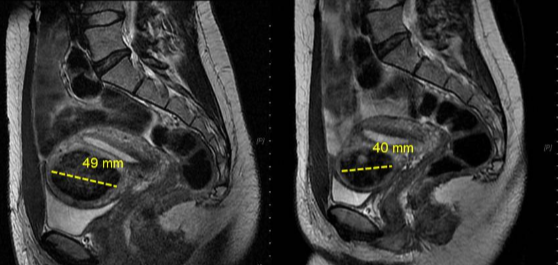

在 12 个月时,子宫肌瘤的大小有所减小。

直径28.4%

容积 35.9%(按体积计算)

所有接受治疗的患者 子宫肌瘤相关症状显著减轻,

生活质量显著提高

44岁,患有盆腔疼痛和阴道出血症状